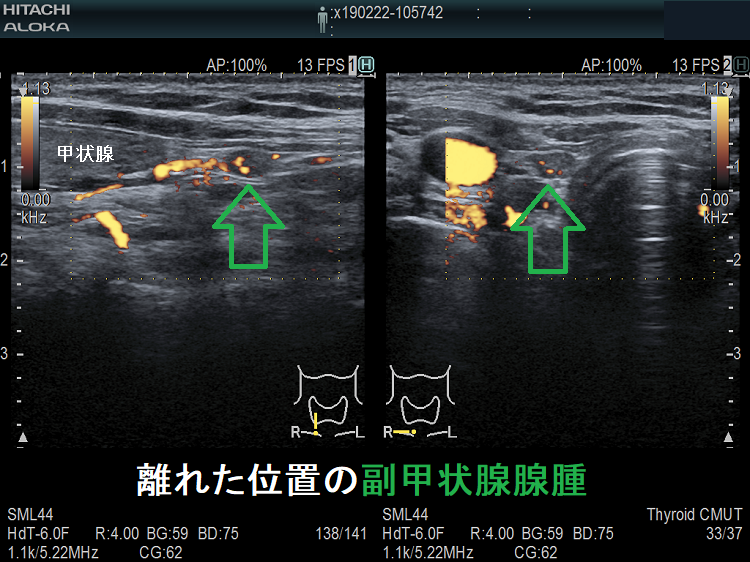

(➸)原因となる副甲状腺腺腫、副甲状腺癌、副甲状腺過形成をデジタルハイビジョン超音波診断装置で診断。エコーでは、甲状腺とのインピーダンスの違いにより、甲状腺-副甲状腺境界部に線状高エコーが生じます(右図の↓)。内部は中心血流を認め、リンパ節でないのが分かります。

微小副甲状腺腫;血清カルシウムは正常範囲内の上限だが、脱水などの影響で上限を超える場合もある。骨密度は正常で、腎結石(腎臓結石)もない。

超音波(エコー)検査で見つからない副甲状腺は、

- 縦隔内

- 食道背側

- 喉頭背側

に存在する場合です。